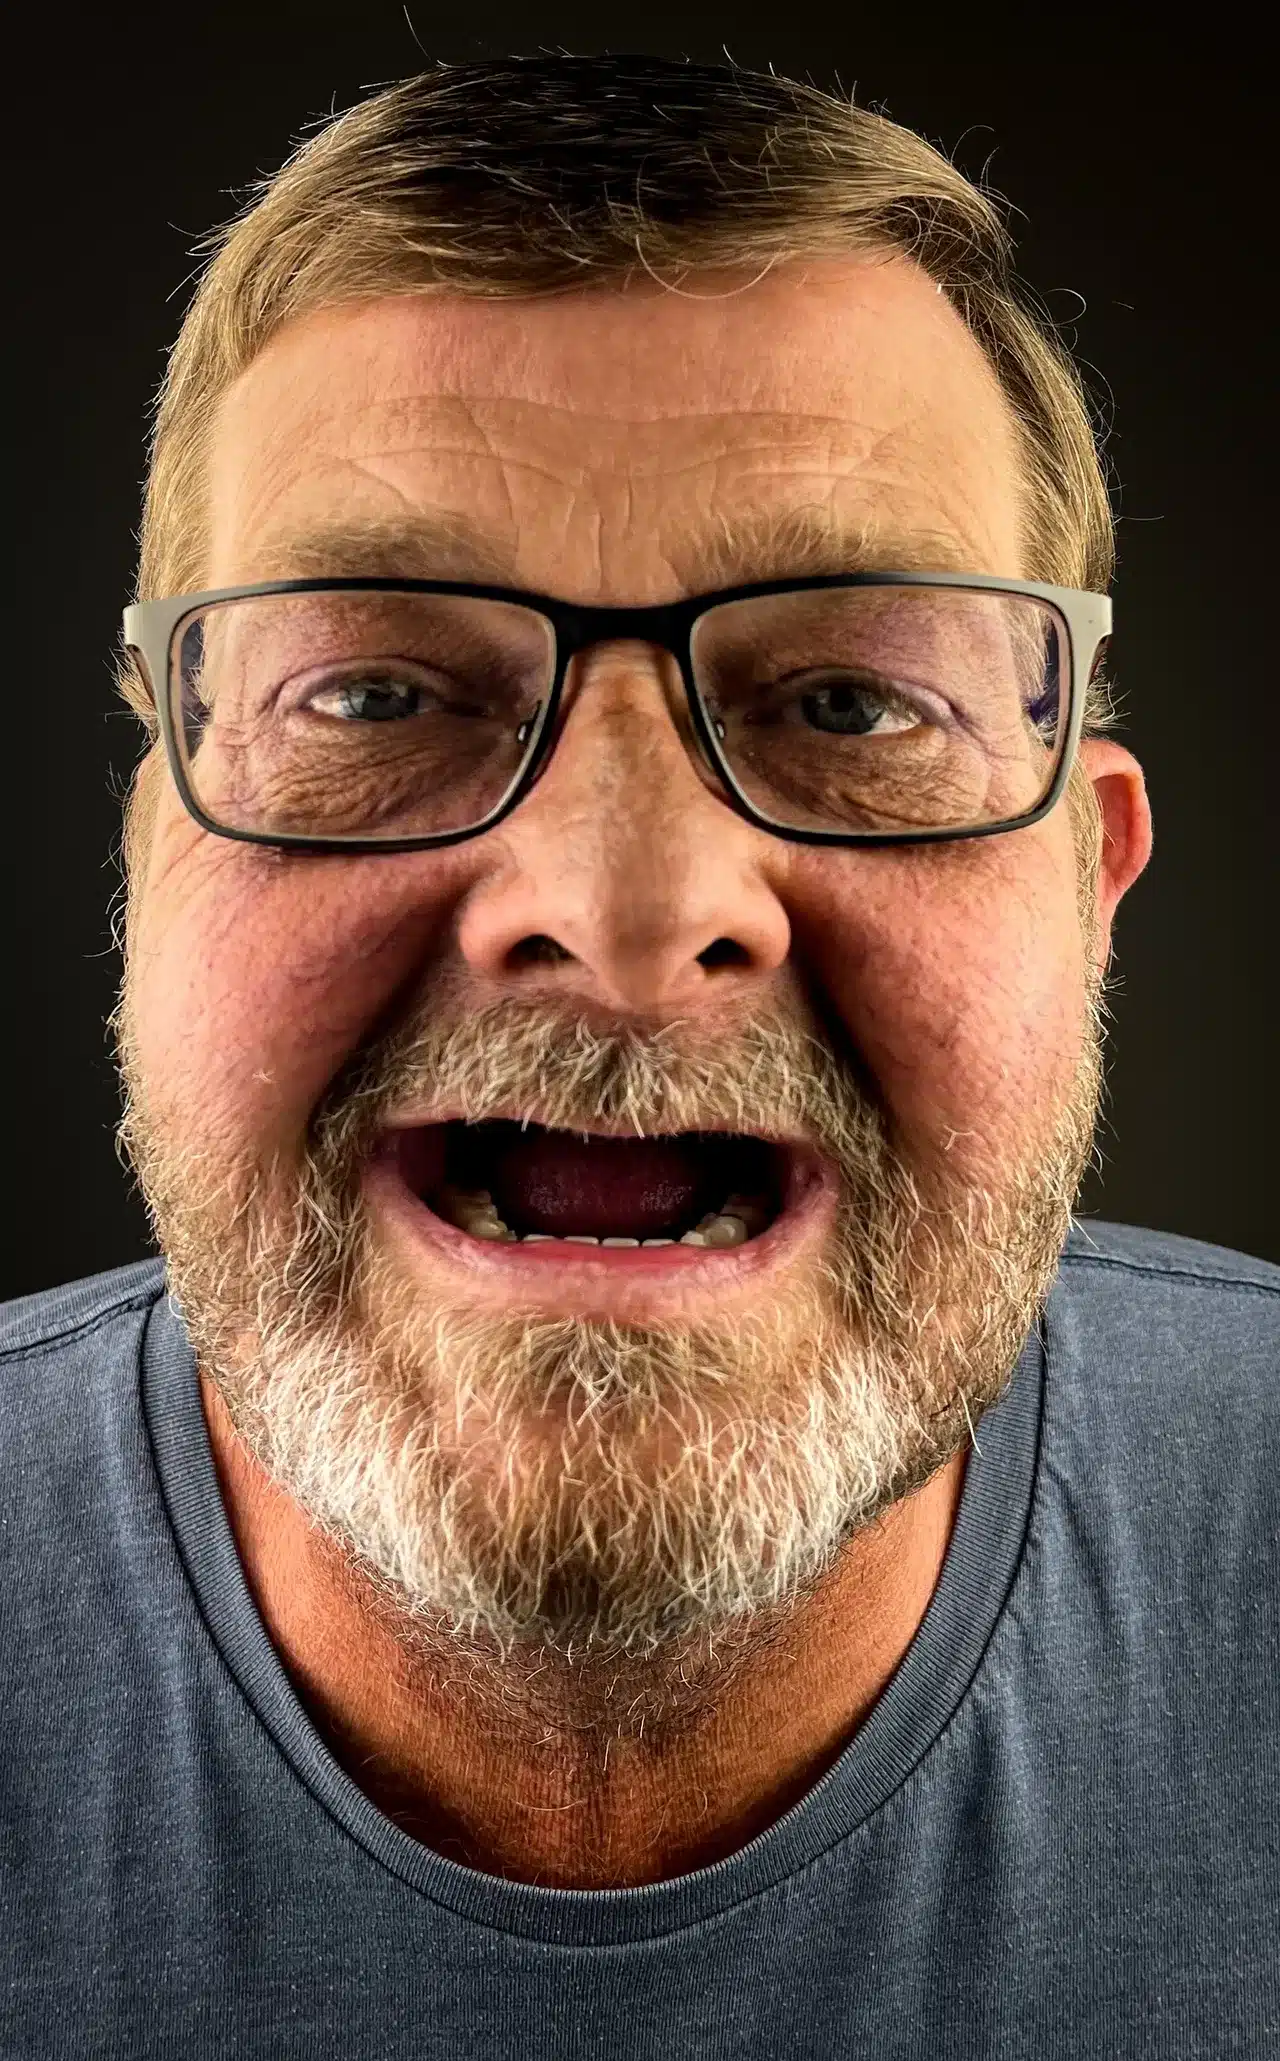

Single Implant Case

Before

After